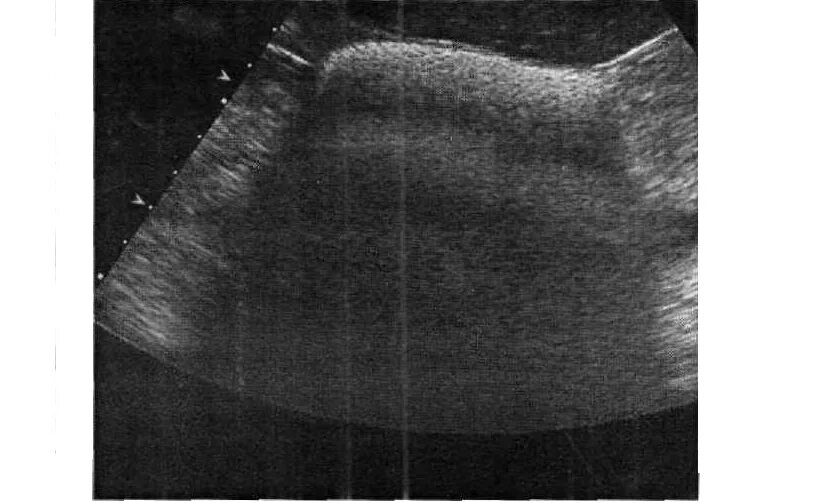

Обследовать брюшную полость